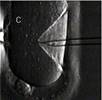

На рисунке ниже изображен процесс введения иглы для инъекции сперматозоида в яйцеклетку.

Рисунок 1. Введение иглы для инъекции сперматозоида в яйцеклетку. При проведении данной процедуры оплодотворение в пробирке происходит в 70-85% случаев.